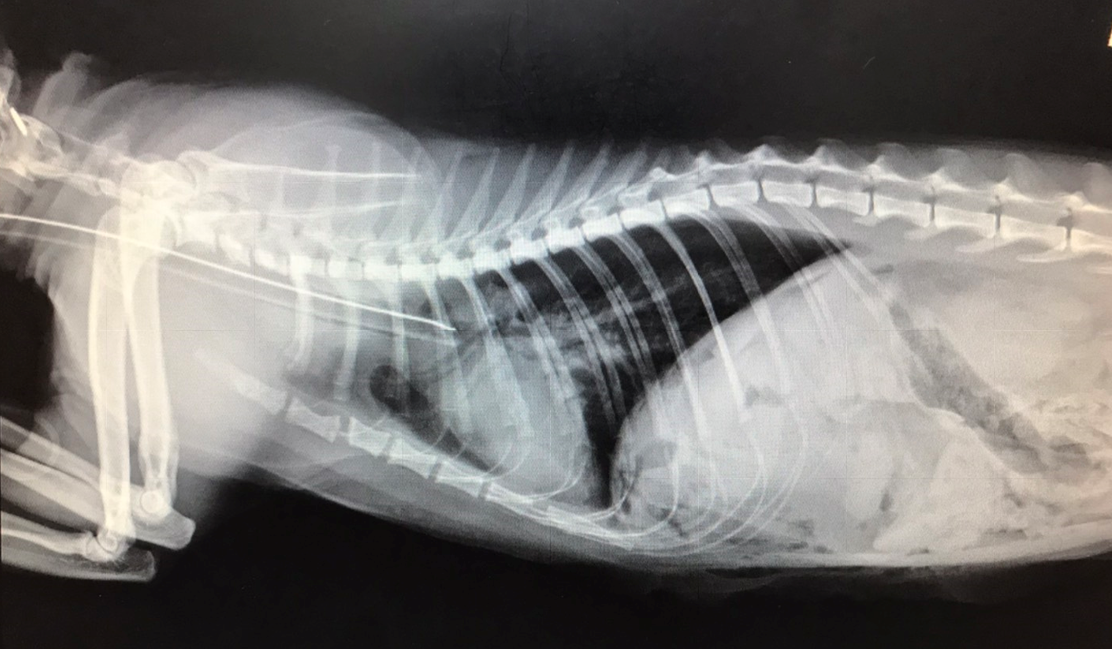

手術後X光,胸腔內異常軟組織影像已經消失

橫膈的邊緣又出現,胸腹腔有完整分界